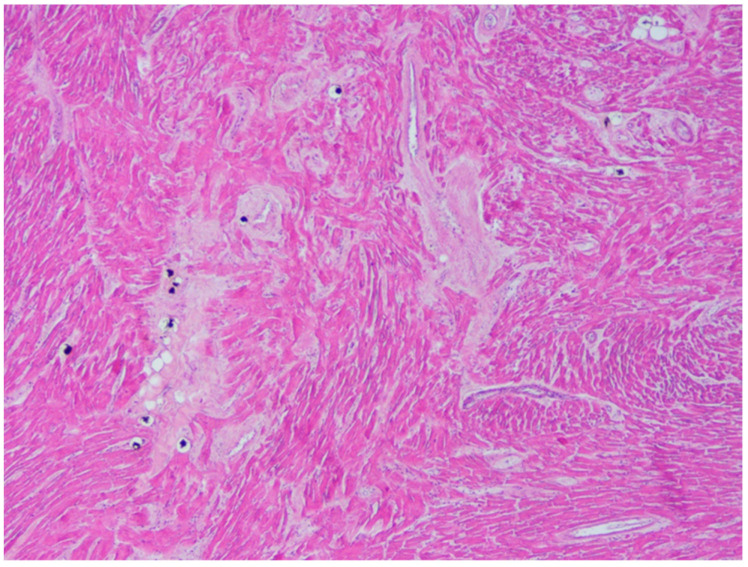

A 20-year-old young man (body mass index: 28) suddenly died in a public place. The friend who witnessed his death declared that he had recently smoked cannabis. All the witnesses said that the young man appeared in good health and that he suddenly collapsed (without any previous symptom). Basic life support maneuvers were promptly started, but when paramedics arrived, he was asystolic at ECG. The public prosecutor requested an autopsy to find the cause of the death. The victim played several competitive sports and had a syncope while playing football three years before. At external examination of the body no relevant sign was found. At the autopsy, performed five days after the death, the heart was isolated and fixated in toto in a 10% buffered formalin-based solution (Figure 1 and Figure 2). Both the lungs appeared swollen (weights: left—450 g, right—940 g), and multiorgan congestion was observed. Heart examination (weight: 530 g, longitudinal diameter: 11 cm, transverse diameter: 13 cm) presented no anomaly. Atria, valves, left ventricle (anterior wall thickness: 1.3 cm; lateral wall thickness: 1.4 cm; posterior wall thickness: 1.7 cm; interventricular septum thickness: 1.5 cm) and right ventricle (wall thickness: 0.5 cm) did not show any macroscopic relevant finding. Coronary circulation was right dominant. Left anterior descending coronary artery presented, at 2 cm from its beginning, a 0.3-cm-thick 5.5-cm-long myocardial bridging (Figure 3). Other coronary arteries were macroscopically normal. The conduction system was carefully analyzed, and serial sectioning targeted blocks of areas of interest [ref. 12,ref. 13]. Histopathological examination of the myocardium (Figure 4) found wavering of myocardial fibers, fibrosis and disarray in the left ventricle myocardial area above the MB (Figure 5); fibrosis in sino-atrial node area (Figure 6) and infiltration of fatty tissue (separated the myocardium) in the antero-lateral region of right ventricle free wall (Figure 7). The atrio-ventricular node presented no microscopic anomalies. No signs of myocarditis were found.

Microscopic examination of the atria and ventricles found some interesting and complex features. Starting from the left ventricle, fibrosis and disarray in the myocardial area above the MB were described. These features have already been associated to MB in young cases of SD [ref. 32,ref. 36]. In particular, considering the young age, the presence of fibrosis and disarray without ventricular hypertrophy in regions far from the septum (as in our case) is compatible with an early phenotype of HCM (but it has also been reported as a sign of MB-related myocardial ischemia) [ref. 32,ref. 36,ref. 37]. It should be considered that the abnormal (>500 g) weight of the heart is also suggestive of HCM.

In our case, there also was a sign suggestive of arrhythmogenic cardiomyopathy (ACM): the fatty infiltration of the right ventricle. However, this feature was only found in the antero-lateral region of the right ventricle, a localization that is typical of physiological conditions [ref. 38]. Moreover, the fatty infiltration was clearly separated by the myocardium, and there were no signs of necrosis/atrophy of the myocytes (that are typical of ACM), no fibrous or fibro-fatty infiltration of the myocardium (common among young cases of ACM) and no inflammatory infiltrates (that can be present, for example, in ACM hot phases, i.e., the phases of acute myocarditis that can suddenly complicate the disease) [ref. 37,ref. 39]. Finally, NGS found no variant pathogenic for ACM. All these data suggest a physiological condition. However, this finding is atypical, because fatty infiltration of the myocardium generally affects elderly or obese patients, and our case was young and non-obese (albeit overweight). Hence, since the absence of signs of cardiomyopathy, a clear pathogenic significance cannot be given to the findings. However, it should be considered that some authors reported that fatty infiltration could cause arrhythmias because it represents a structural barrier to the heart electrical impulse and causes oxidative stress. In particular, previous cases of sudden death in patients with fat of the free wall of the right ventricle have been reported [ref. 40].